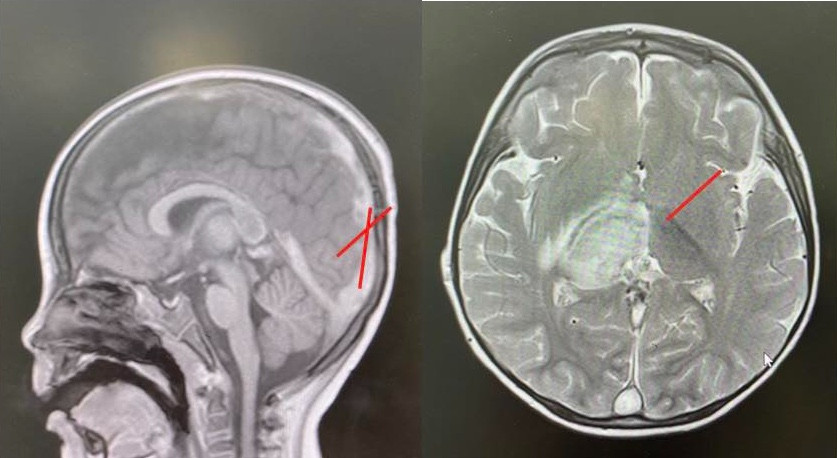

Chụp CT scan sọ não cấp cứu ghi nhận nhồi máu đồi thị kèm phù não xung quanh, huyết khối lan tỏa tĩnh mạch vỏ não, xoang tĩnh mạch nội sọ, kéo dài đến tĩnh mạch cảnh chung trái, đường giữa lệch sang trái. Chụp MRI sọ não cũng ghi nhận hình ảnh nhồi máu. Xét nghiệm dịch não tủy bình thường.